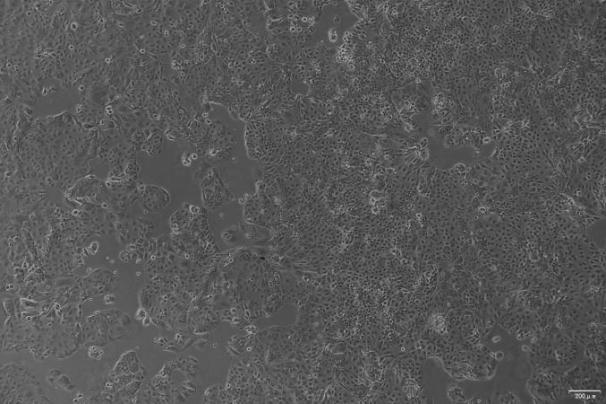

人肾透明细胞腺癌细胞系(786-O)来源于一名 58 岁患有原发性透明细胞腺癌的高加索男性,是一种肾癌的亚型,该细胞具有微绒毛和桥粒的特性,可在软琼脂中生长,这些细胞可产生一种类似于肽的 PTH,与乳腺和肺肿瘤产生的肽相同。该肽具有与 PTH 类似的 N 末端序列,具有 PTH 样活性,分子量为 6000 道尔顿,是研究 PTH 相关疾病,如骨质疏松症等的理想模型。

贴壁生长;上皮细胞样 |